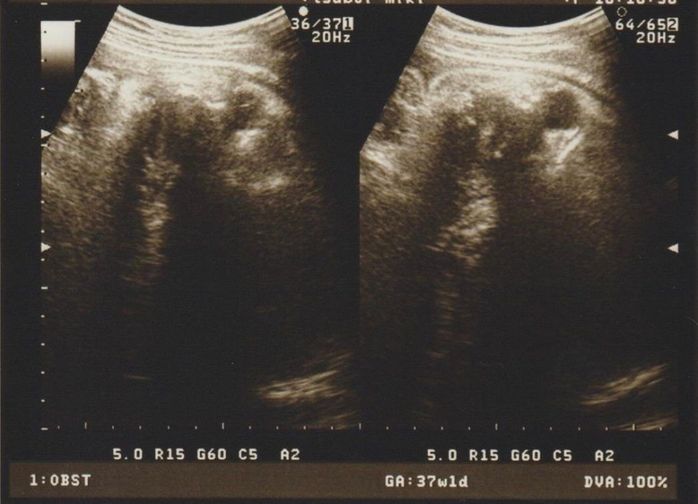

「もういつ生まれてもいいよ」 - 妊娠37週目のエコー写真

推定体重2441g 「もういつ生まれてもいいよ」とのお言葉をもらう

先生に「頭が下がってきていて、おなかも張りやすくなってきているから、予定日より早く生まれるでしょう」と言われました。助産師さんにおっぱいマッサージもしてもらい、ちゃんと母乳も出て「いよいよだな」と気持ちも高ぶります。胎動も少なくなってきていて、赤ちゃんが大きくなっているのを胎動の感じ方の変化からも体感できました。